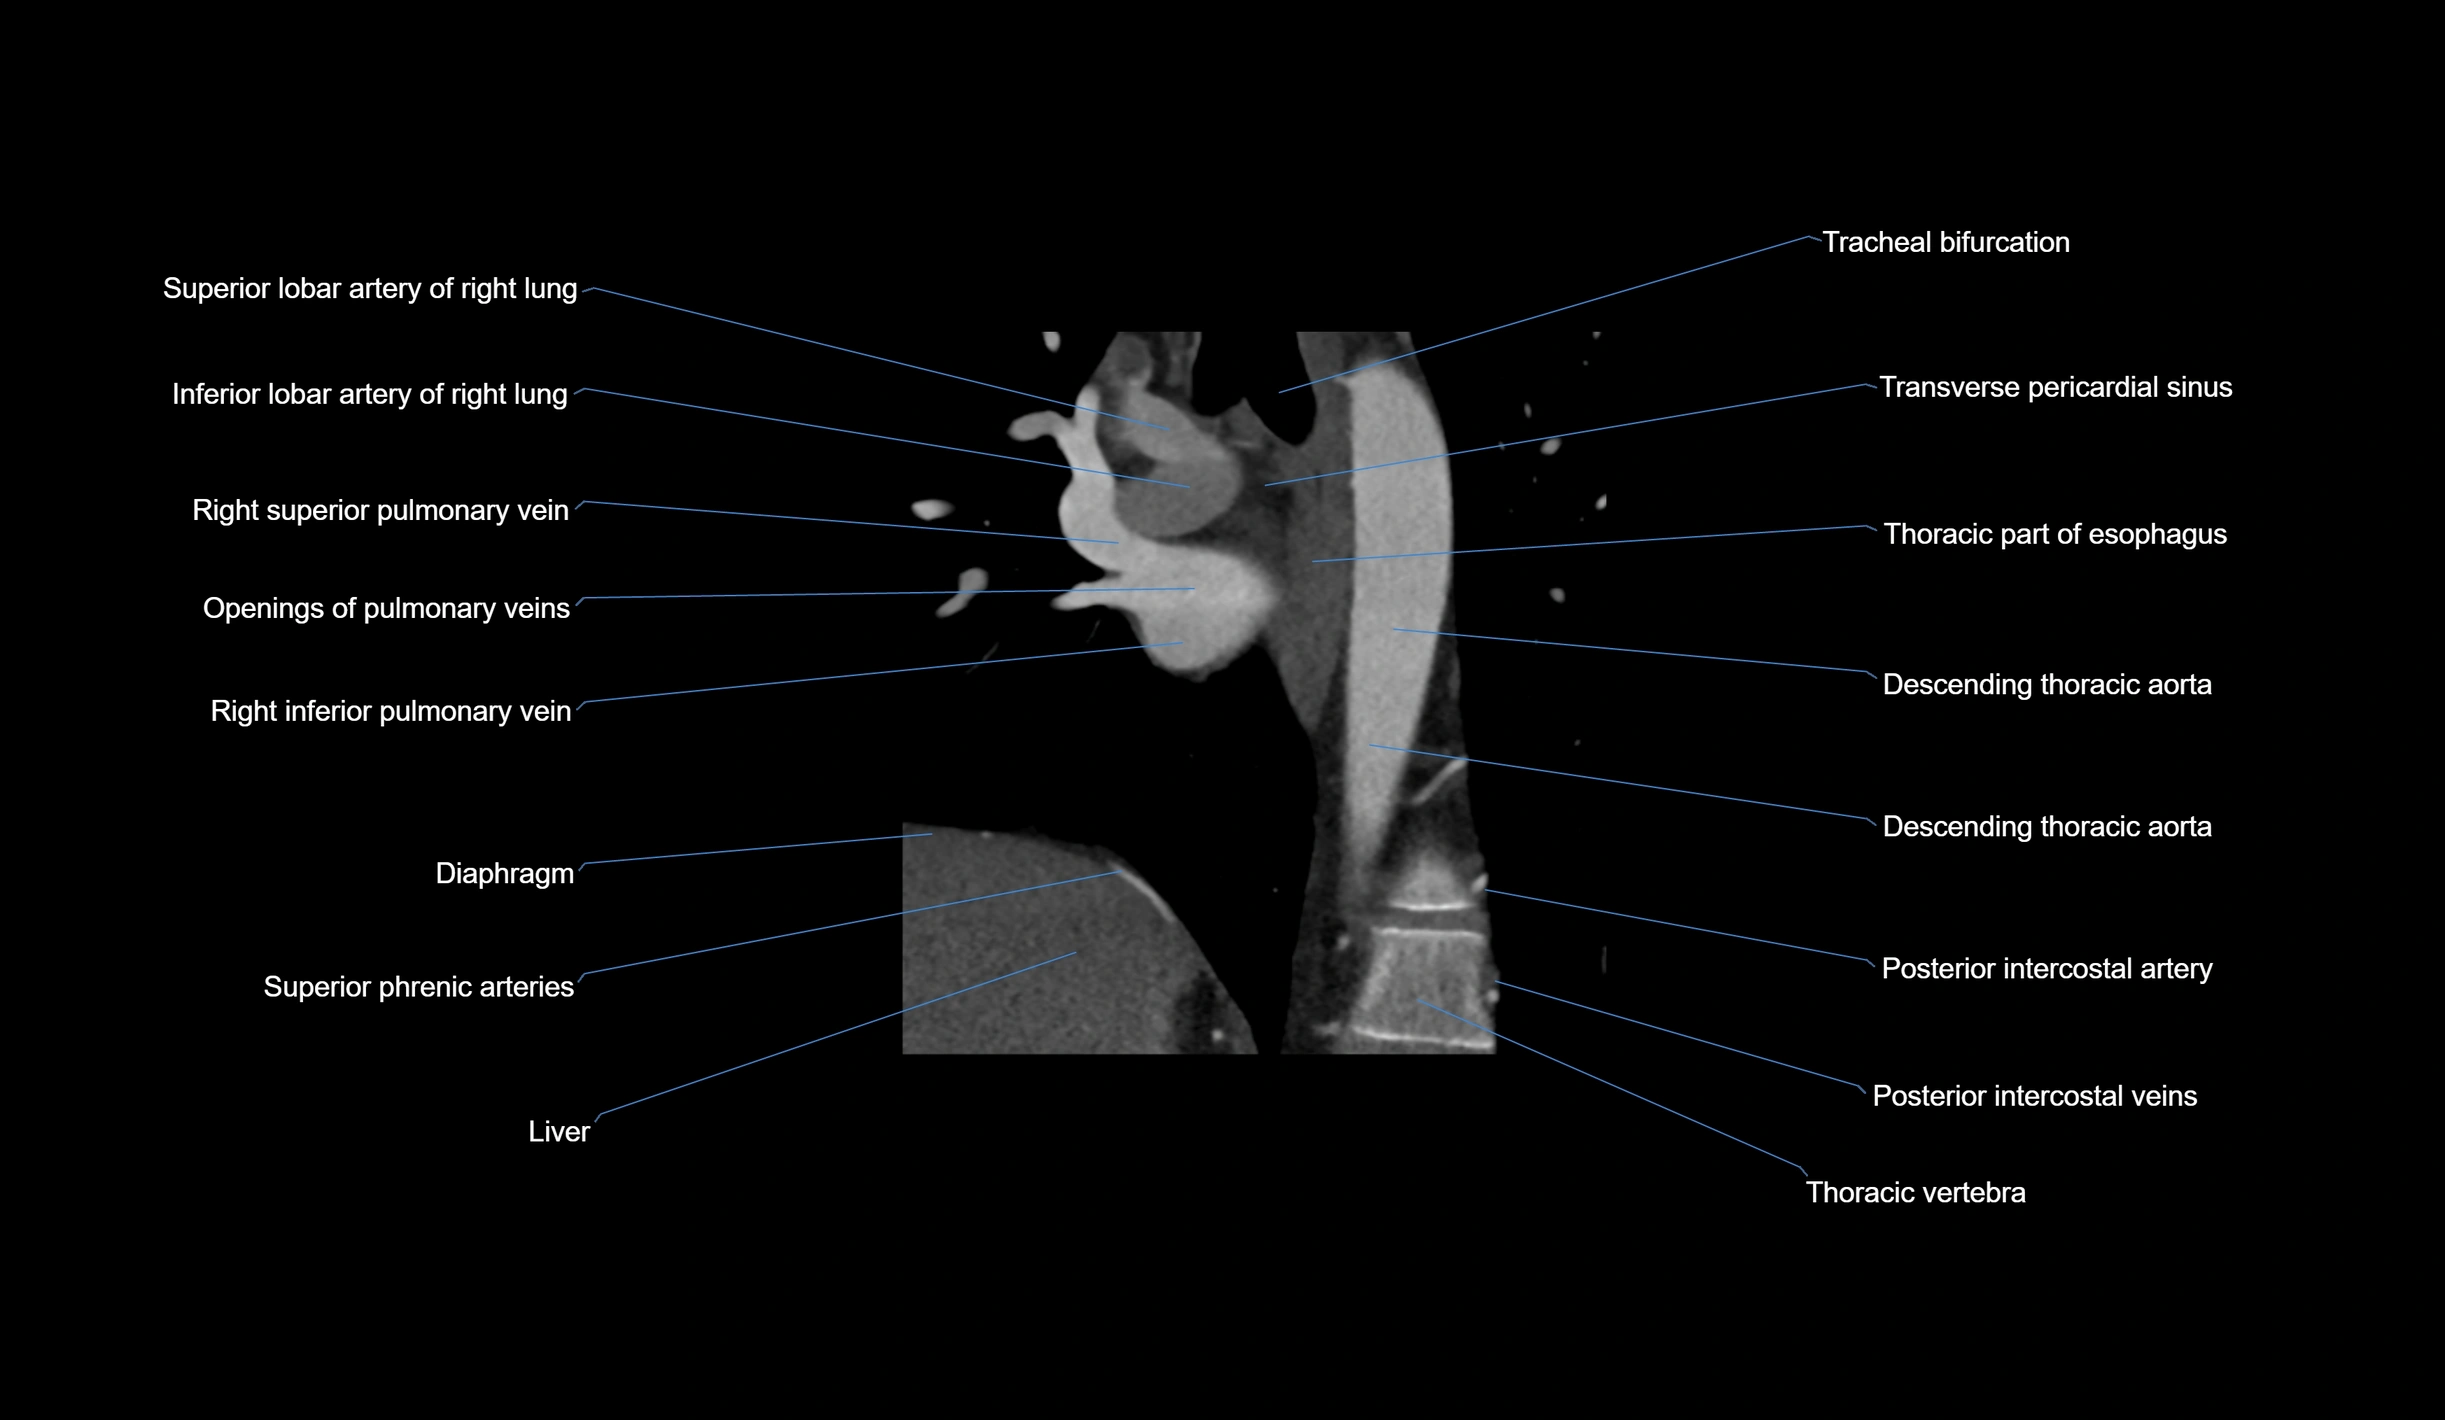

- Acute marginal artery (AM)

CT Appearance

CT Coronary Angiography (CCTA):

-

Best non-invasive modality for acute marginal artery visualization

Shows origin, course along the acute margin, and right ventricular branches

Detects stenosis, occlusion, calcified and non-calcified plaques, aneurysm, or anomalous course

Multiplanar reformats and 3D reconstructions help in pre-PCI and surgical planning

Critical for assessing right ventricular infarction risk in RCA disease

MRI image

CT images